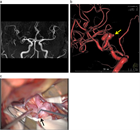

1. 未破裂脳動脈瘤の診断は、カテーテル法によるDSA:digital subtraction angiographyおよびその3次元血管撮影像がゴールドスタンダードである。3D-CTA:3次元ヘリカルコンピュータートモグラフィー、MRA: magnetic resonance angiographyなどは低侵襲な代替え診断法として未破裂脳動脈瘤の診断および治療に用いることが妥当である(推奨度1、J)